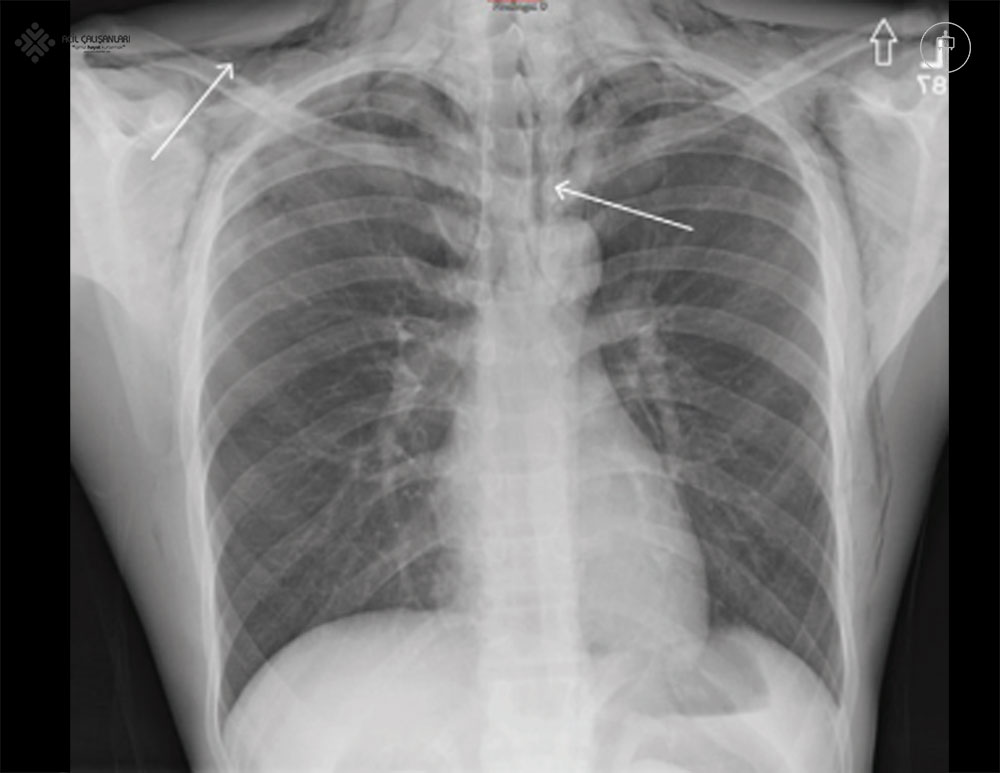

Çoğu toraks yaralanması, fizik muayene ve akciğer grafisi ile değerlendirilebilir. Göğüs röntgeni hızlı, kolay erişilebilir, düşük maliyetli ve genellikle travma değerlendirmesinde ilk basamak görüntüleme yöntemidir. Travma bölümünde herhangi bir müdahale uygulanan her hastaya, işlemin yeterliliğini doğrulamak için kontrol amaçlı bir göğüs röntgeni çekilmesi önerilir.

Künt Torasik Travmada Göğüs Röntgeni

Künt torasik travma sonrası başvuran her hastada ilk değerlendirme için göğüs röntgeni çekilmesi önerilir. Ancak, travma küçükse ve hastada altta yatan yaralanmayı düşündürecek fiziksel bulgular yoksa, göğüs röntgeni zorunlu değildir.

- İlk değerlendirme genellikle akciğer grafisi ile yapılır.